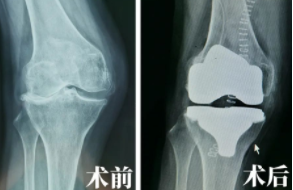

来到我院后,关节外科张传开主任为张大姐进行了仔细检查,结合相关片子判断其为“双膝骨性关节病”。在经过相关术前讨论及手术准备后,张传开、郝亮手术团队决定为其在Mako机器人辅助下行右侧人工膝关节置换术。

Mako关节置换机器人辅助全膝关节置换术基于CT进行3D的智能建模,个性化定制术前方案。同时,术中根据患者具体软组织张力进行动态调整,根据病人的具体情况实施精准化、个性化操作。

在Mako机器人的辅助下,张大姐的手术进行的很顺利。手术中对于截骨、假体安装等重要环节都进行了全程三维定位,并实时将角度、大小、骨质覆盖等重要信息通过数字影像及时传达给手术医生,帮助医生做出准确判断,这种客观数据的评判标准与传统手术只能凭借医生“自主认为”的方式相比,无疑更加精准、更加科学,这对患者术后的康复来说也大有益处。